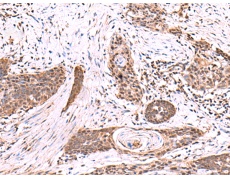

IHC positive control:

Human tonsil and Human esophagus cancer